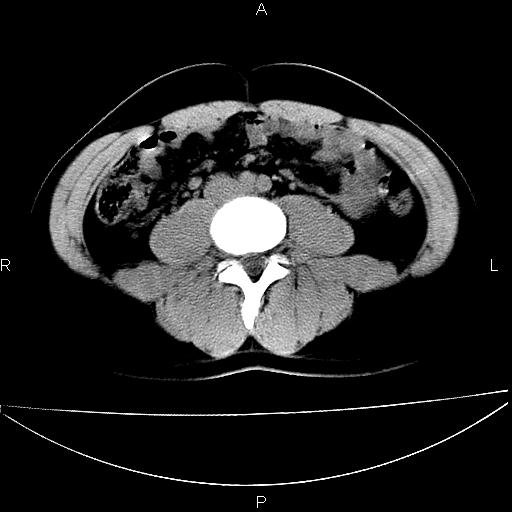

标题: CT29462:双测输尿管扩张

男 25岁 自述 尿频尿急,排尿困难20多天.无腰痛, b超说左肾盂轻度积水,左输尿管上端扩张.未见结石影. ct我看双侧肾盂轻度积水,双输尿管上端都扩张,大家看看能看见结石吗?

双输尿管扩张下端未见高密度结石和输尿管晕轮征,不好说是结石.增强后如何?

未见明确输尿管结石,mru效果还好

双侧输尿管上端扩张,未见明确结石,可进一步ivp检查。

双侧输尿管上端扩张,未见明确结石,可进一步ivp检查。支持!